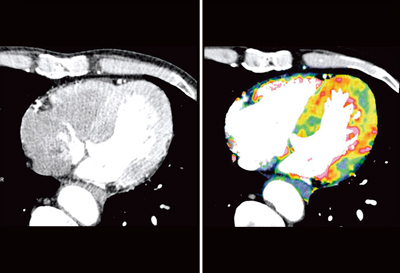

心拍数50〜111bpmと変動が大きかったが,冠動脈はきれいに描出され,RCAとLCXの狭窄が示唆された(図1)。curved MPR画像(図2)では,RCAはほぼ閉塞し,LCXにも強い狭窄が見られた。LADは石灰化のため,はっきりとした評価が難しかった。

![]() 図1 症例1:冠動脈CTのVR画像 |